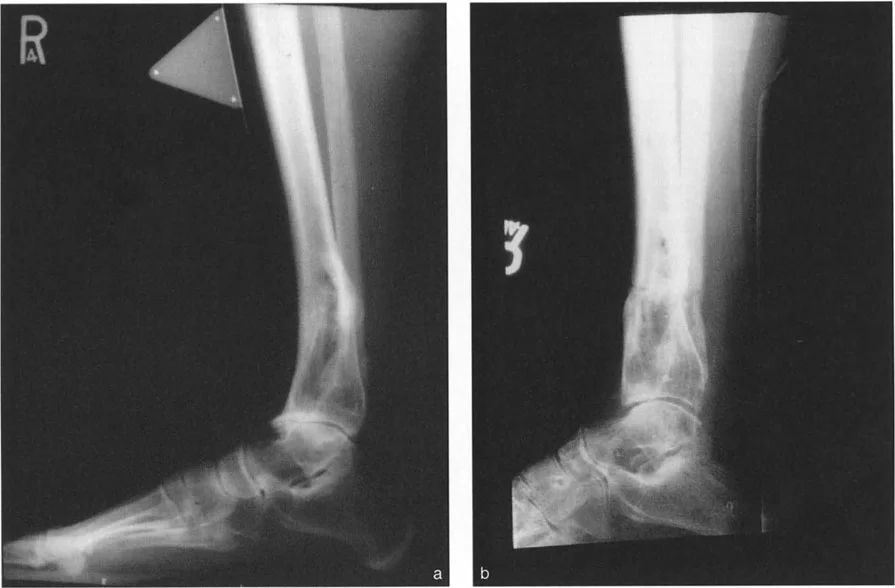

* الأشعة السينية (X-rays) الواقفة لكامل الطرف السفلي: هذه الأشعة ضرورية لتقييم المحاذاة الكلية للطرف السفلي تحت تأثير وزن الجسم. يطلب الأستاذ الدكتور محمد هطيف صورًا شعاعية كاملة الطول للساق أثناء الوقوف (Full-length standing alignment films) لتقييم المحور الميكانيكي للساق وتحديد زوايا المفاصل بدقة.

* الأشعة السينية الجانبية والامامية الخلفية للكاحل: تُظهر هذه الصور تفاصيل مفصل الكاحل نفسه، بما في ذلك زاوية القصبة الأمامية البعيدة (ADTA) وزاوية القصبة الوحشية البعيدة (LDTA)، وهي زوايا حاسمة لتحديد التشوه في المستويين الأمامي والسهمي.

أنواع جراحات قطع العظم فوق الكاحل (Supramalleolar Osteotomy)

جراحة قطع العظم فوق الكاحل (SMO) هي الإجراء الأكثر شيوعًا لتصحيح تشوهات قصبة الساق البعيدة. تتضمن هذه الجراحة قطعًا دقيقًا في عظم الساق (القصبة) فوق مفصل الكاحل مباشرة، ثم إعادة محاذاة العظم وتثبيته في الوضع الصحيح. هناك عدة أنواع من هذه الجراحة: